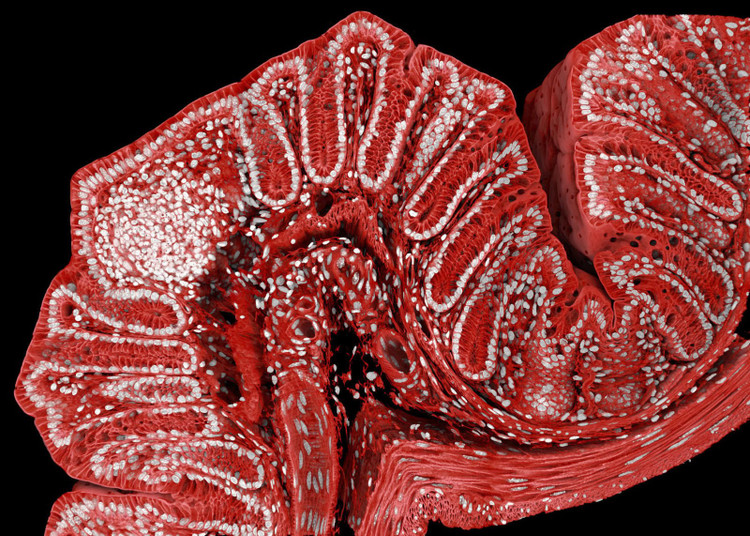

Tikus memainkan peranan penting dalam penyelidikan saintifik. Imej kolon tikus ini diambil oleh penyelidik di Institut Penyelidikan Bioperubatan Friedrich Miescher di Switzerland, menggunakan mikroskop resonans magnetik, teknik biasa dalam sains bioperubatan untuk mengkaji sel yang dilabelkan dengan probe pendarfluor.